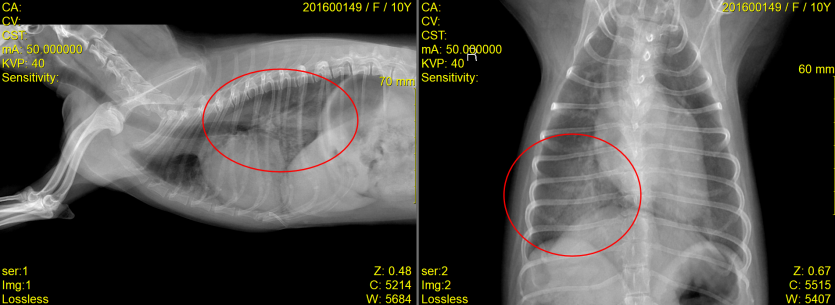

내원 후 흉부 방사선 사진 촬영과 심장 초음파 검사 진행

저희 잠실ON동물의료센터에서는 복슬이의 정확한 증상 파악을 위해 흉부 방사선 사진촬영과 심장 초음파 검사를 진행하였습니다.

갑작스러운 호흡곤란의 원인은 심장질환 중, 예후가 불량한 건삭 파열인 것으로 확인되었습니다.

다행히 집중적인 입원치료 끝에 11살 말티즈 복슬이는 4일만에 폐수종이 사라지고 건강히 퇴원하게 되었습니다.